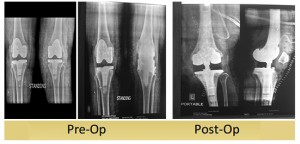

Revision TKR with RHK and Trabecular Metal Cone

61 years female suffering from Rheumatoid Arthritis underwent Left Total Knee Replacement 2008. She fell down 8 months back and since then she is unable to bear weight on operated leg (due to periprosthetic fracture)

Managing such cases is a challenge as there is severe bone loss associated with fracture. But ... Read more..